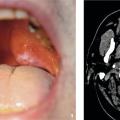

Lichen plan